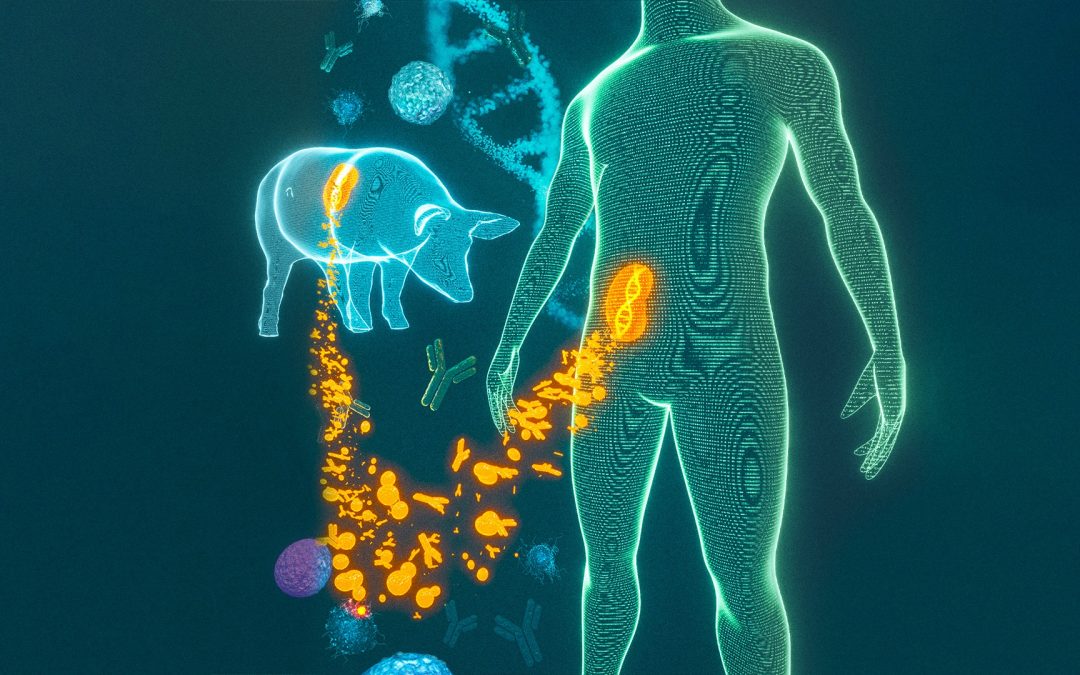

Suite au succès de la première xénotransplantation d’un rein de porc sur un patient humain en août 2023, des avancées significatives ont été réalisées grâce aux analyses moléculaires menées par les équipes du Paris Institute for Transplantation and Organ Regeneration...